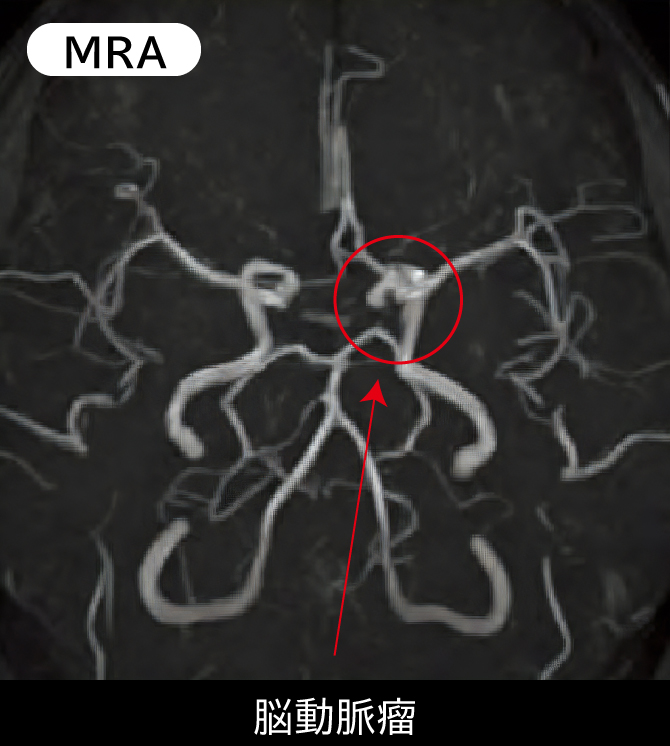

MRI・MRA検査は、X線を使用せず、強力な磁場を利用して頭部を撮影します。脳の断層写真を撮影し、脳腫瘍や脳梗塞を鮮明に写し出す「MRI」、脳の血管を立体的に写し出し、血管が狭くなっているところや脳卒中の前兆を発見する「MRA」という2種類の検査があります。MRAは、MRIとセットでお受けいただく必要があります。